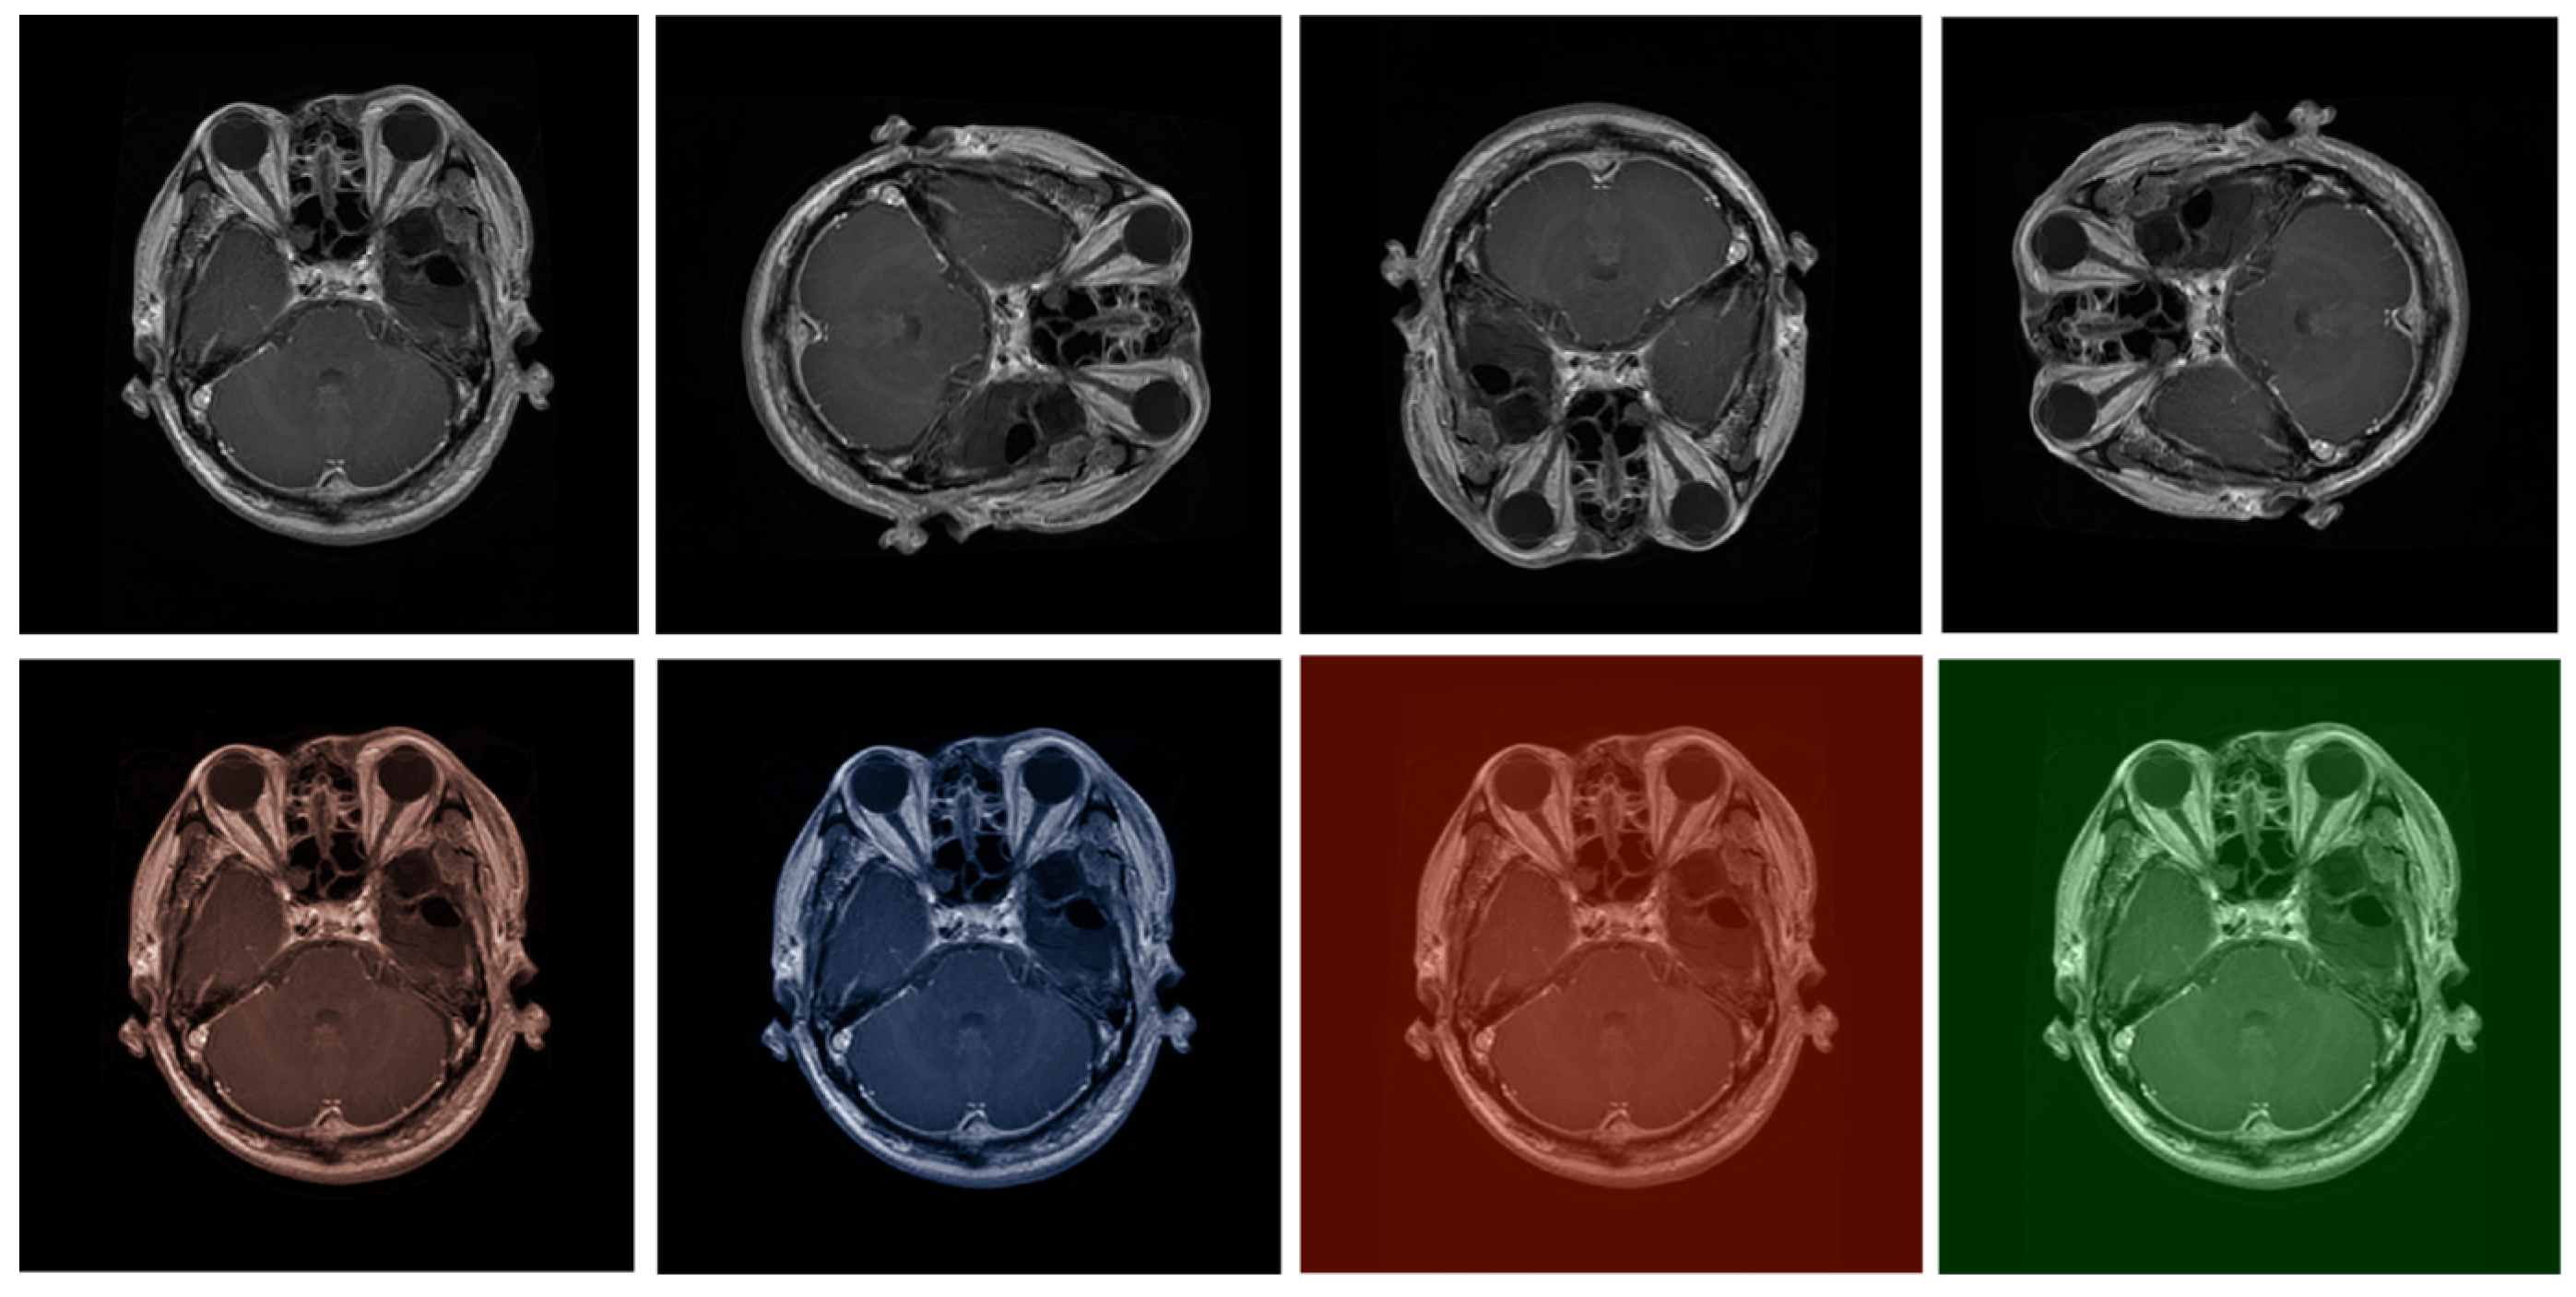

- To further improve the feature refinement process, we integrate an enhanced spatial attention mechanism into the model. This helps focus on the most relevant areas of the input image, enhancing the overall quality of the super-resolved output, which is crucial for medical image interpretation.

- We conduct extensive experiments using specialized medical imaging datasets, demonstrating the efficacy of the proposed model in terms of both quantitative metrics and qualitative results. The proposed model outperforms existing state-of-the-art models, showcasing its potential for real-world medical applications.

- We provide a detailed analysis of the proposed model’s performance compared to other leading SISR models. Our results highlight the advantages of our modifications in handling the unique challenges presented by medical images, such as the preservation of subtle anatomical details and noise reduction.